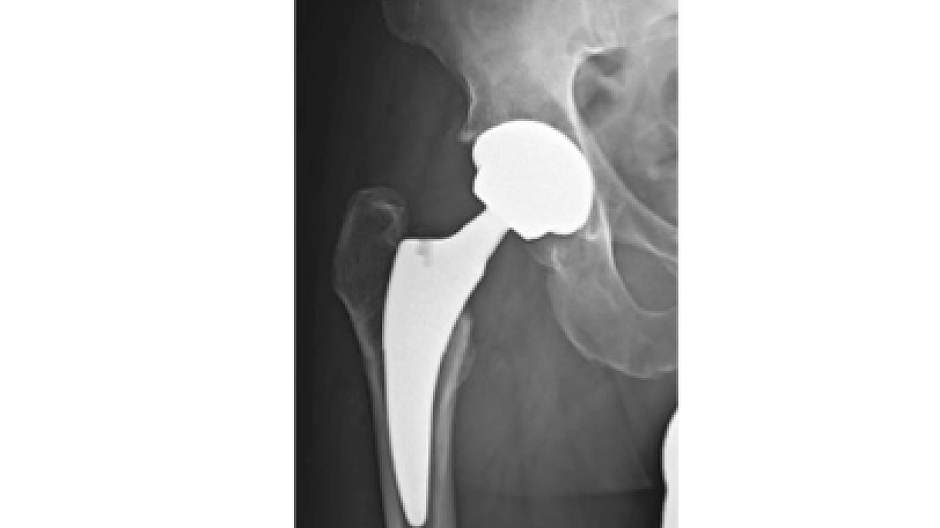

Fotos Unfallchirurgie und Orthopädie